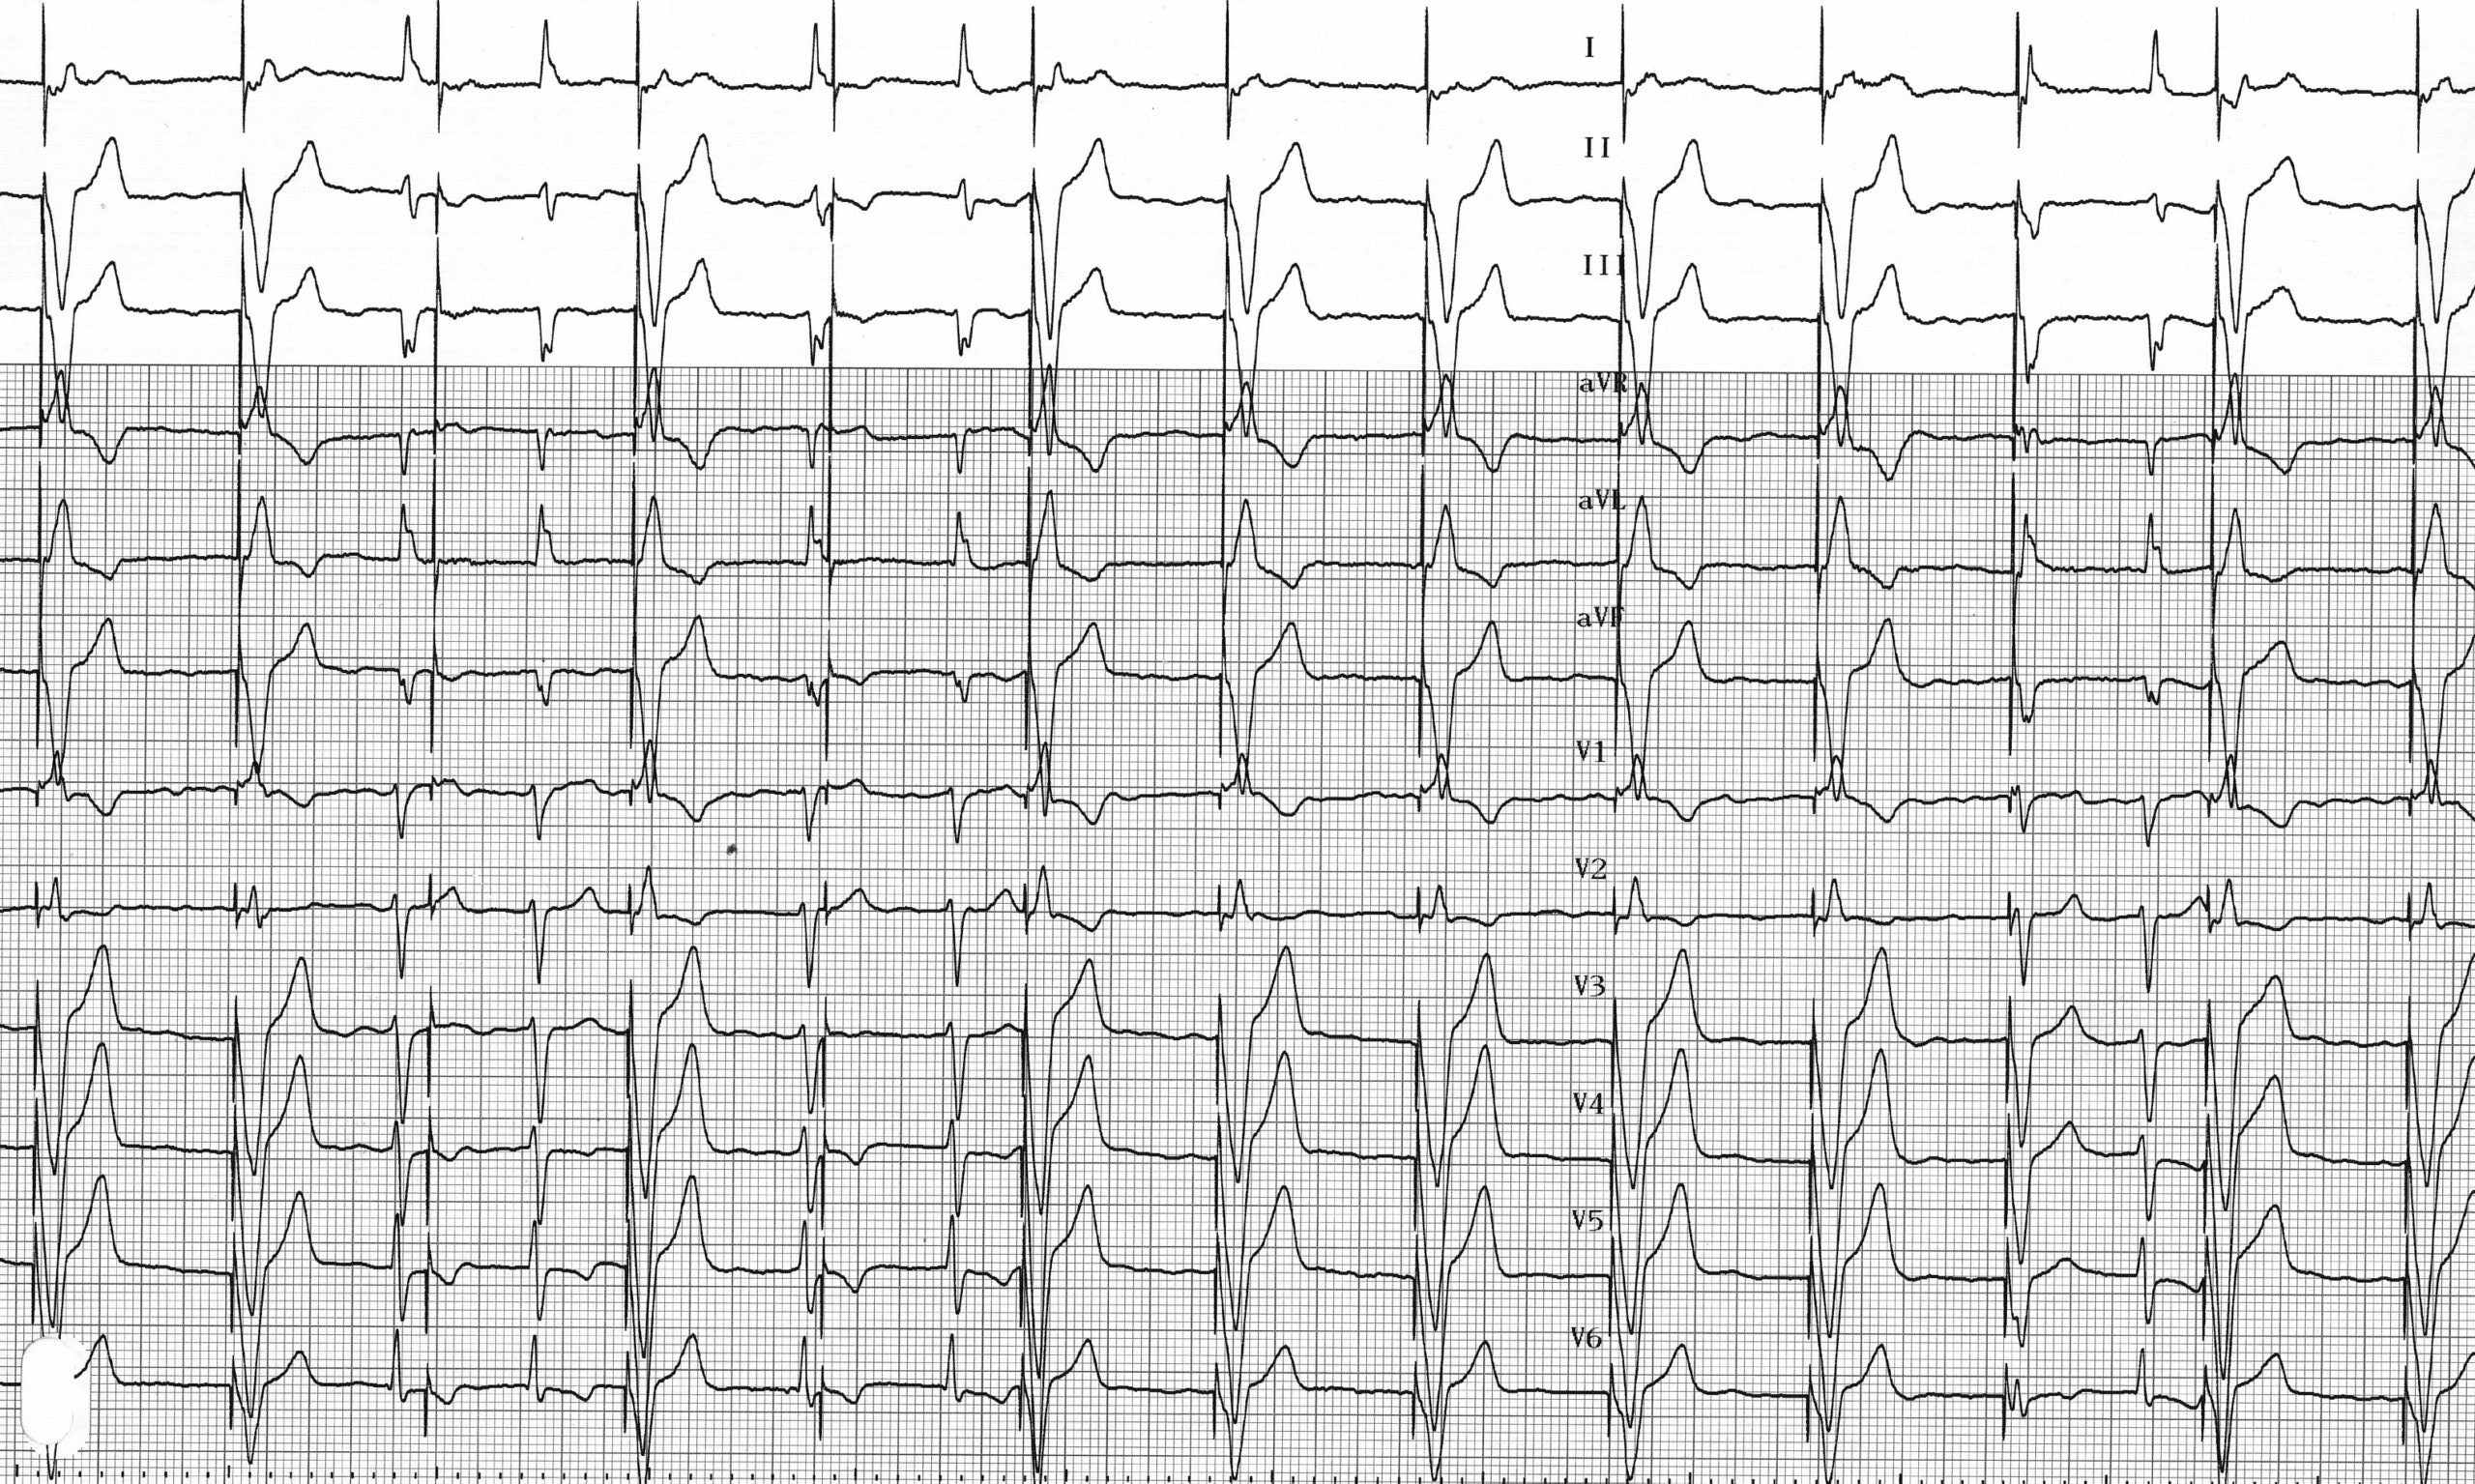

Tracé 4.8: Défauts de détection ventriculaire

Homme implanté d’un stimulateur fonctionnant en mode VVI dans le cadre d’une maladie de l’oreillette (alternance entre dysfonction sinusale et épisodes de fibrillation auriculai­ re); électrocardiogramme de contrôle

L’électrocardiogramme montre une fibrillation auriculaire; les QRS spontanés ne sont pas détectés et n’inhibent pas la stimulation ventriculaire qui est efficace; défauts de détection ventriculaire;

Ce tracé révèle une sous-détection ventriculaire entrainant parfois une stimulation en période vulnérable. En l’absence de détection correcte, le stimulateur fonctionne en mode asynchrone avec impossibilité d’inhibition sur les ventricules spontanés. Il existe un risque théorique faible mais non nul d’induction d’une arythmie ventriculaire polymorphe maligne compromettant la survie du patient. De plus cette stimulation inutile entraine une consommation d’énergie préjudiciable pour la durée de vie de l’appareil.

La programmation d’une sensibilité ventriculaire adaptative plus adaptée a permis de corriger le problème chez ce patient.

Une sous-détection atriale ou ventriculaire se traduit sur l’électrocardiogramme par l’existence d’artéfacts de stimulation à fréquence fixe en dépit de l’existence de complexes spontanés qui n’inhibent pas la stimulation.